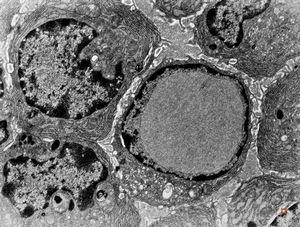

normal seromucinous salivary gland